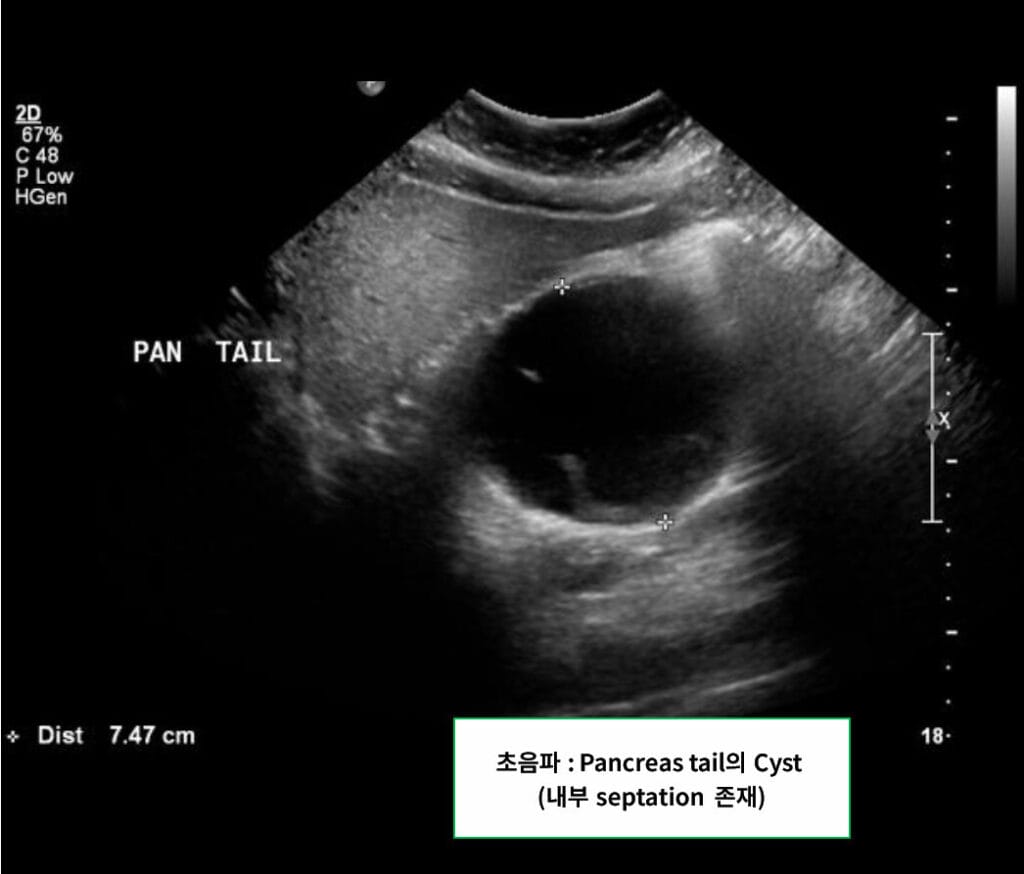

영상 소견

췌장 체부/미부에 단일성, 격벽성 낭종으로 나타나며, 췌관과 연결되지 않습니다.

| 🟦 Unilocular or septated cyst in pancreatic body/tail |

| 단일성 또는 격벽성 낭종이며, 주변 장기로 압박을 줄 수 있습니다. |

| 🟦 No communication with pancreatic duct |

| IPMN과 달리 췌관과 연결되지 않습니다. |